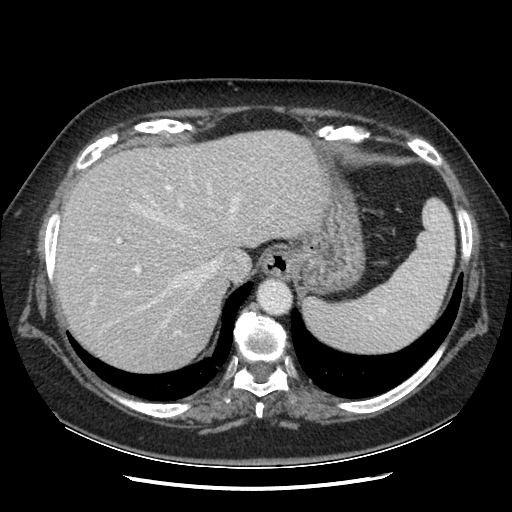

Original NATIVE CT scan (input)

Full window (WL 1023.5, WW 4095 β†’ Low βˆ’1024, High +3071)

Generated VENOUS CT scan (A→B translation)